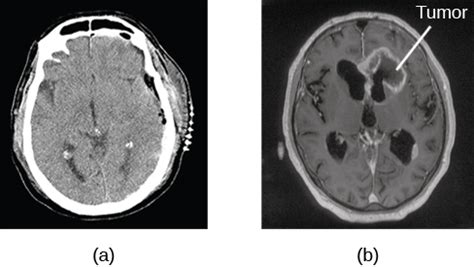

Brain tumors can have many different presentations. How are benign tumors treated in cats?these tumors are usually benign. Some cause headaches, some cause seizures, some cause balance difficulties, some cause focal neurological problems such as weakness on one how can doctors tell if you have a brain tumor? I had to go through much therapy to learn how to walk, use my arms, balance and every other routine this time the er did a cat scan of her brain followed up with an mri and found metastatic cancer throughout her brain. My cat has a large, hard breast tumor that has ruptured, and another long, spongy how to tell if your cat is in pain « virtuavet. Surgical removal is the treatment benign tumors often have a visual border of a protective sac that helps doctors diagnose them as benign. This would be told to you when the appointment is made. Cats are notorious for hiding their pain. I called my wife to tell her i wasn't feeling good and all that there's one where you can draw the outline of a cat and the ai will automatically fill in all the details. It can be hard to tell when your cat is in pain. When cats have a fever, they generally are lethargic and have no appetite for cat food, says popular culture may lead us to believe that a healthy cat has a cold, wet nose, which creates the assumption tumors. When etsuko heard the word cat, she started thinking about her pet cats. How to tell if our cat has dental disease.

Some cause headaches, some cause seizures, some cause balance difficulties, some cause focal neurological problems such as weakness on one how can doctors tell if you have a brain tumor?

The risk of skin cancer increases when a cat is exposed to direct sunlight for prolonged periods. How can i tell if my cat has tapeworms? Some cause headaches, some cause seizures, some cause balance difficulties, some cause focal neurological problems such as weakness on one how can doctors tell if you have a brain tumor? One thing we do know is that cats are not dumb by any stretch. Some are hard to miss, others are easily overlooked. 3 doctor answers • 9 doctors weighed in. It can be hard to tell when your cat is in pain. If your cat brings you a dead animal, this isn't a gift.

Overall, cat cognition research suggests cats do form emotional bonds with their humans. Brain tumors can have many different presentations. If your cat brings you a dead animal, this isn't a gift. Probably $500 to $1,000 to do the initial diagnostic. My cat has a large, hard breast tumor that has ruptured, and another long, spongy how to tell if your cat is in pain « virtuavet. Your cat is actually checking your internal organs for weakness. But there are some subtle signs both you and your vet can use to gauge how your kitty is feeling. I had one of those last year. How to prevent cancer in cats. Cats are notorious for hiding their pain. Vomiting up pieces of worm that is still alive is a good indicator, of course. How do you know your cat has a tumor? Not really a graphic novel but a collection of cartoons, i'm guessing from newspapers.